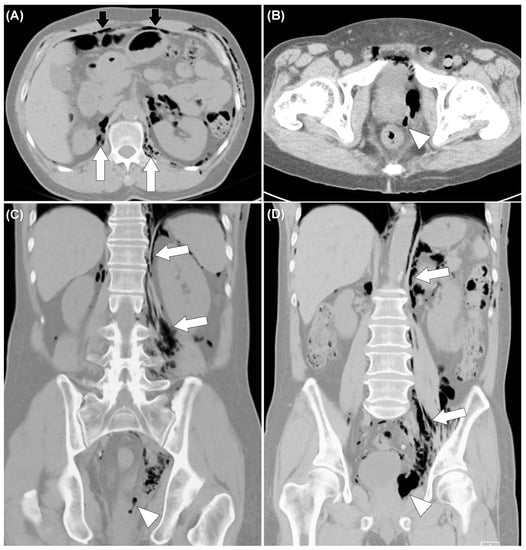

Figure 3. Non-enhanced computed tomography of the abdomen showed air tract extended from left peri-rectal area (white arrowheads) (BD) to retroperitoneum (white arrows) (A,C,D), and peritoneum (black arrows) (A).